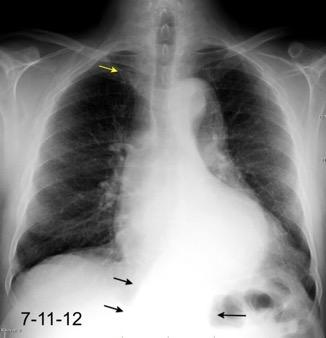

Tromboembolismo pulmonar Diafragma elevado 20%

25. ELEVACIÓN UNILATERAL. TEP

Consolidación por Infarto pulmonar. (TEP)